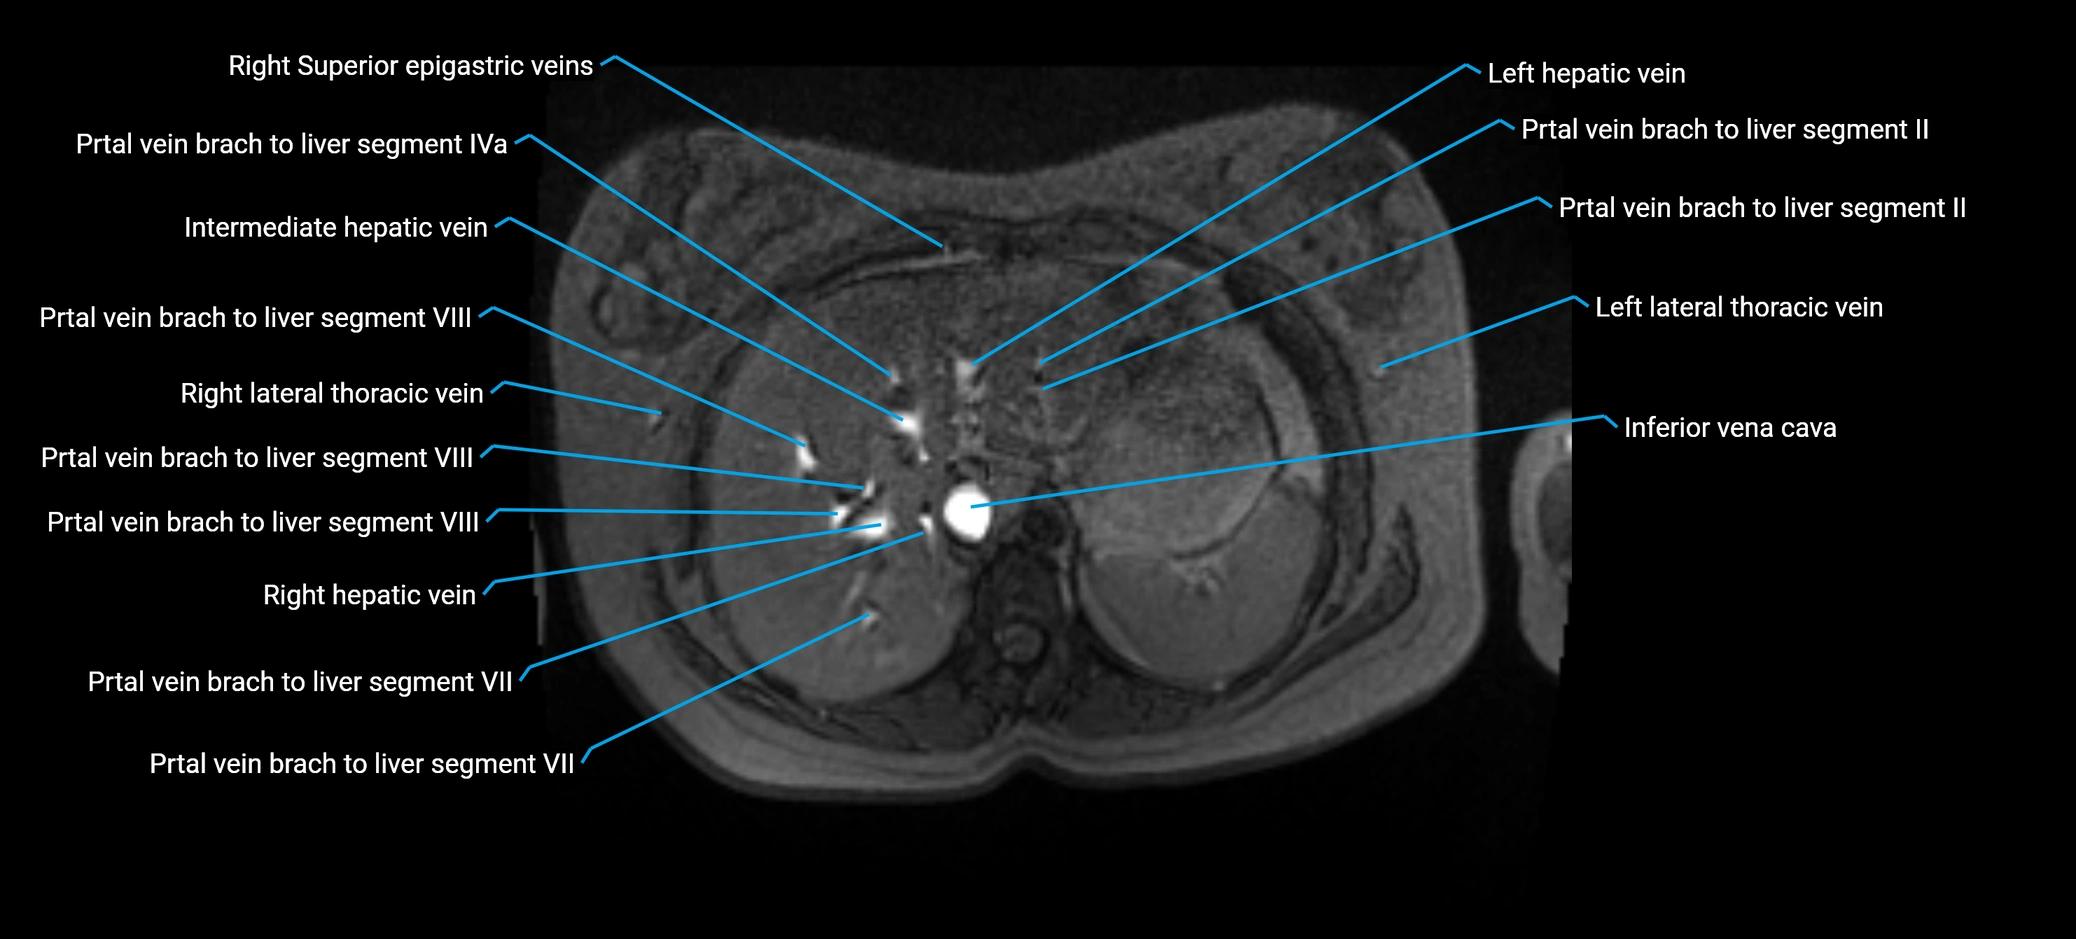

MRV TOF (Time-of-Flight MR Venography):

• Appears as a bright, high-signal vascular channel representing flowing blood

• Clearly shows branching pattern of right portal vein into anterior and posterior branches

• Best in coronal or axial reconstructions for segmental mapping

• No need for contrast, relies on flow-related enhancement

Post-Contrast T1 Fat-Sat GRE:

• Enhances brightly and homogeneously during the portal venous phase

• Clearly delineates branching into segments V and VIII

• Best sequence for evaluating patency, caliber, and anatomic variants

• Early arterial phase: minimal enhancement

• Delayed phase: gradual washout but still brighter than hepatic parenchyma

MRI image

image